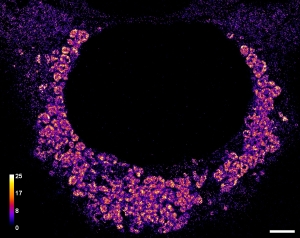

Nanometer-scale distribution of PD-1 in the melanoma tumor microenvironment

The nanometer-scale spatial organization of immune receptors plays a role in cell activation and suppression. While the connection between this spatial organization and cell signaling events is emerging from cell culture experiments, how these results translate to more physiologically relevant settings like the tumor microenvironment remains poorly understood due to the challenges of high-resolution imaging in vivo. Here we perform super-resolution immunofluorescence microscopy of human melanoma tissue sections to examine the spatial organization of the immune checkpoint inhibitor programmed cell death 1 (PD-1). We show that PD-1 exhibits a variety of organizations ranging from nanometer-scale clusters to more uniform membrane labeling. Our results demonstrate the capability of super-resolution imaging to examine the spatial organization of immune checkpoint markers in the tumor microenvironment, suggesting future direction for both clinical and immunology research.

Colin J. Comerci, Dannielle G. McCarthy, Mehdi Nosrati, Kevin B. Kim, Mohammed Kashani-Sabet, W. E. Moerner, and Stanley P. Leong, “Nanometer-scale distribution of PD-1 in the melanoma tumor microenvironment,” J. Radiol. Oncol. 7, 020-025 (2023) (DOI: 10.29328/journal.jro.1001048, published online 10 May 2023).